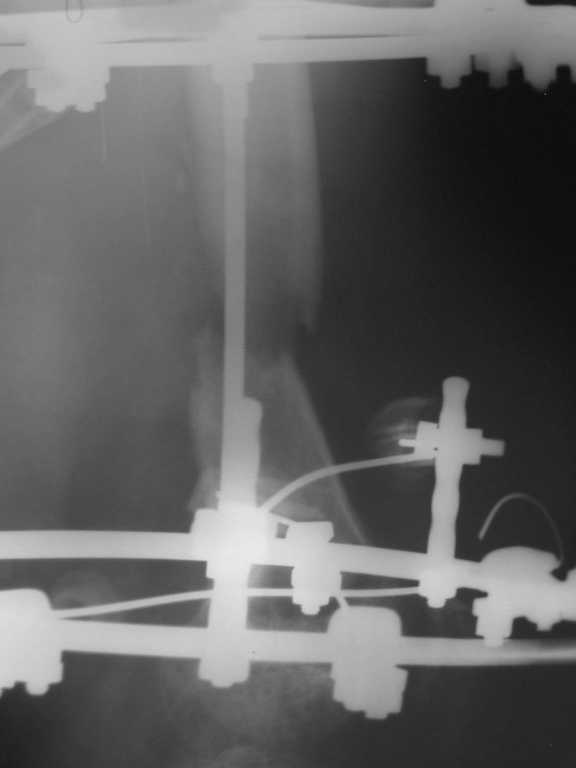

Уважаемые коллеги. Возникли затруднения с выбором оптимальной тактики ведения и лечения больного с огнестерльным ранением правого бедра. Пациент лечился в областной больнице в течении почти двух месяцев, после чего был отправлен на амбулаторное лечение. Травма была получена на Новый Год, прострелили правое бедро сигнальной ракетницей, был многооскольчатый перелом правой бедренной кости, сквозное ранение мягких тканей с обширными ожогами правой и левой конечностей 2 - 3 степени. При поступлении была выполнена ПХО раны, ожогов, наложены асептические повязки. Через две недели наожен аппарат Илизарова для постепенной компрессии отломков. На протяжении 1,5 месяцев проводилась компрессия - в результате отломки стали соприкасаться, укорочение конечности составило примерно 6 см. Рана мягких тканей к этому времени практически закрылась. С этим результатом в начале марта больной был отправлен на амбулаторное лечение по месту жительства (см. рентгеннограммы). Ему были даны рекомендации - продолжить компрессию в течении 6 недель по 1,5 мм в неделю, контрольный снимок через месяц. Пациент следовал рекомендациям,продолжал компрессию и в апреле отослал снимки в областную больницу на консультацию(см. рентгенограммы). Ему посоветовали продолжить компрессию еще на месяц. Последние снимки были сделанны в мае и опять он получил рекомендации продолжать компрессию. После этого он пришел ко мне на консультацию с вопросом - что ему делать. Мое мнение: поскольку наблюдается обширный дефект костной ткани, я бы рекомендовал провести оперативное вмешательство и восплнить этот дефект аллотрансплантантом костной ткани. Трансплантант сыграет роль депо минеральных веществ и заодно ускорит восполнение дефекта. А после этого вторым этапом провести уже удлинение конечности. На ваш взгляд какой тактики лучше придерживаться - продлжать компрессию или провести операцию по восполнению дефекта?

Рентгенограмма от 06.03.2008

2008_03_06_F.jpg